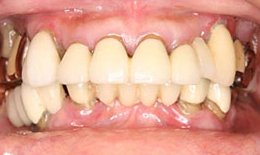

治療前

上顎

保存困難な歯を抜歯後、インプラントを7本埋め込み、ボーンアンカードブリッジを装着した

下顎

保存困難な歯を抜歯後、インプラントを5本埋め込み、セラミックスクラウンを被せた